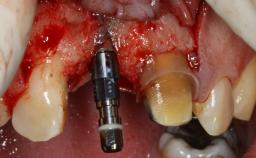

Management of a Fractured Implant Supporting a Screw-retained Metal-ceramic Restoration

The fracture of an implant after it has been restored is one of the most severe complications. It most frequently occurs in partially edentulous jaws (1.5%). Most implant fractures involve implants with a diameter of 3.75 mm made of commercially pure titanium (Eckert 2010). Unfortunately, many cases are not reported or documented by the clinicians involved in resolving the problems created by the fracture. This case report describes the management of an implant fracture at site 36 in a middle-aged male patient. The implant had been restored with a screw-retained metal-ceramic crown.